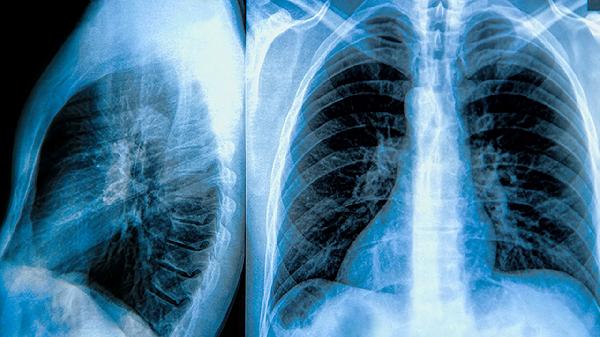

肺部疾病患者除遵医嘱用药外,应保持室内空气流通,避免烟雾粉尘刺激。饮食宜清淡,适量食用百合、银耳等润肺食材,戒烟限酒。急性感染期需配合血常规、胸片等检查明确病因,慢性病患者建议定期复查肺功能。若用药后出现呼吸困难加重或持续发热,应立即就医。